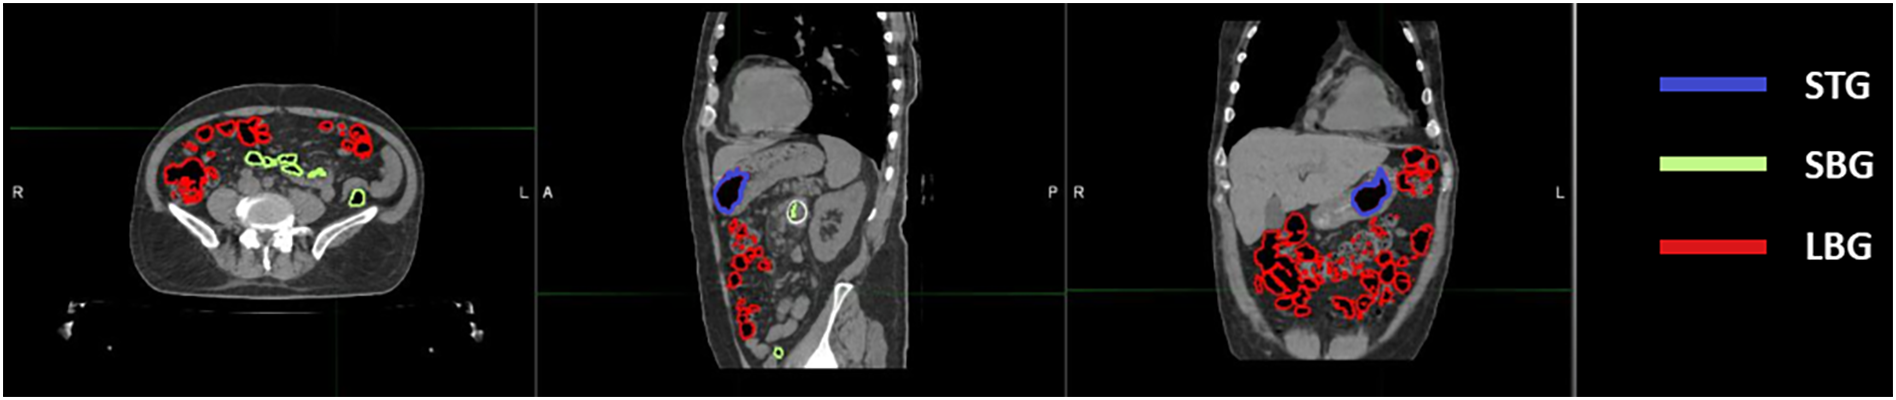

Twenty-one CT scans, one for each different patient undergoing SBRT for gastrointestinal lesion were retrospectively evaluated. All the scans were acquired using the radiotherapy department simulation CT scanner (Discovery Optima, GEhealthcare, Madison, WI) with the same standard GI protocol. Our center’s protocol provides a CT acquisition with 120 kV, 135 mA, slice thickness 1.25 mm, in plane resolution 1.27 x 1.27 mm2 and the maximum field of view for all GI patients. The following anatomical structures were contoured during the treatment planning process: Gross Tumour Volume (GTV) and relative 3 mm isotropic expansion (PTV), the Gastrointestinal Organs at Risk (GIOARs), including stomach (ST), small bowel (SB), large bowel (LB) and gas pockets in the abdominal cavity (GAS). Three additional specific volumes of gas pockets were also defined and contoured: the intersection of GAS volume with each GIOAR obtaining stomach gas volume (STG), small bowel gas volume (SBG) and large bowel gas volume (LBG) (Figure 1). We did not deem it appropriate to add the duodenum to the list of GIOARs containing gas pockets due to the scarcity of gases present within its lumen in the sample of patients analyzed. All contouring were performed by a radiation oncologist with at least 5 years of experience. The normality of the distribution of the mean values of the Hounsfield Units (HU) of pixels contained in GAS, STG, SBG and LBG volumes for all CT scans was tested singularly using a Kolmogorov-Smirnov test (p=0.05). Mean value of HU values of the pixels contained in GAS structure of all patients was converted in RED using the calibration curve of the CT scanner and the obtained value has been named as Gastrointestinal Gas relative Electron Density (GIGED). Finally, differences of mean values of HU of the pixels included in GAS, STG, SBG and LBG using a Wilcoxon-Mann-Whitney test for unpaired samples with a threshold p-value of 0.05 were computed.

Figure 1

Location of abdominal gas volumes divided by the organ at risk in which they are located. A patient’s CT is shown with gas pockets in the stomach highlighted in blue, those in the small bowel in green and those in the large bowel in red.